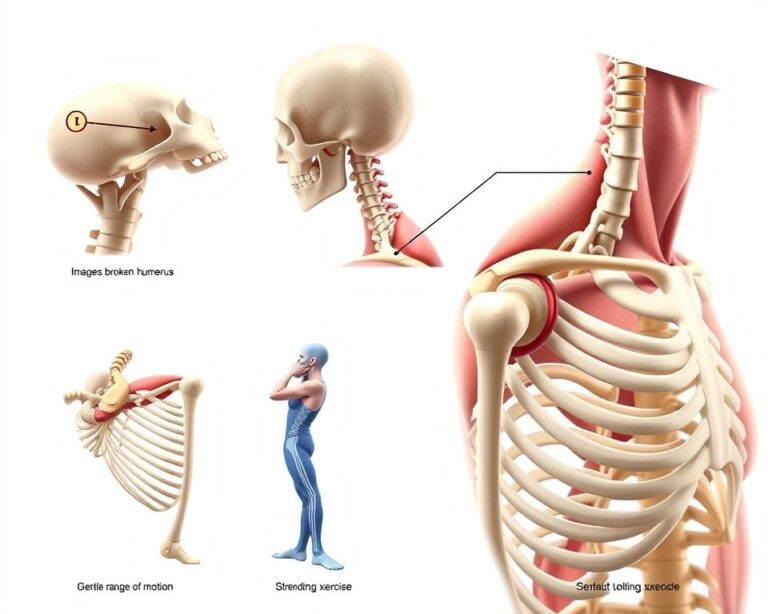

Rodzaje złamań i ich podział

W górnej części uda wyróżnia się kilka charakterystycznych typów uszkodzeń. Złamania wewnątrztorebkowe obejmują okolicę szyjki kości udowej, podczas gdy urazy zewnątrztorebkowe dotyczą obszarów poniżej głowy. Najrzadsze są uszkodzenia w obrębie głowy kości udowej – stanowią zaledwie 1-3% przypadków.

Kryteria oceny uszkodzeń i obraz diagnostyczny

Klasyfikacja Gardena skupia się na stopniu przemieszczenia odłamów kostnych. W stopniu IV kości całkowicie tracą kontakt, co wymaga natychmiastowej interwencji. System Pauwelsa analizuje kąt płaszczyzny złamania – im większy, tym wyższe ryzyko powikłań.

Operacyjne zespolenie kości i endoprotezoplastyka

Dynamic hip screw (DHS) to złoty standard w stabilizacji wewnętrznej. Ta metoda sprawdza się szczególnie przy stabilnych złamaniach szyjki. U osób aktywnych fizycznie często stosuje się endoprotezoplastykę – całkowitą lub częściową wymianę stawu biodrowego.

Program ćwiczeń podczas rehabilitacji

Skuteczny powrót do sprawności wymaga precyzyjnie dobranych technik terapeutycznych. Nowoczesne metody łączą elementy pracy mięśniowej z kontrolą nerwowo-mięśniową, tworząc spójny system odbudowy funkcji motorycznych.

Ćwiczenia izometryczne i ich znaczenie

Napięcia statyczne stanowią fundament pierwszych etapów terapii. Napinanie mięśnia czworogłowego uda w pozycji leżącej poprawia ukrwienie tkanek. Równolegle wprowadza się rotacje stawu skokowego – proste ruchy zapobiegają obrzękom.

Wartość tych metod potęguje zastosowanie poizometrycznej relaksacji. Technika polega na naprzemiennym napinaniu i rozluźnianiu mięśni pośladkowych, co zwiększa elastyczność włókien mięśniowych.

Ćwiczenia dynamiczne oraz rozciąganie

Gdy organizm jest gotowy, wprowadza się elementy aktywnego ruchu. Unoszenie wyprostowanej kończyny z oporem taśmy zwiększa siłę mięśniową. Ćwiczenia w pozycjach półwysokich z piłką gimnastyczną rozwijają koordynację.

Kluczowe jest stopniowe rozszerzanie zakresu ruchu w stawie biodrowym. Delikatne rozciąganie mięśni kulszowo-goleniowych wykonuje się przez 15-20 sekund, zawsze po rozgrzewce. Więcej o bezpiecznym zwiększaniu aktywności fizycznej znajdziesz w naszym specjalistycznym przewodniku.